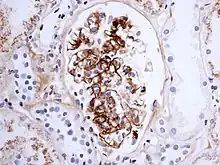

If there is doubt about the cause of the skin lesions, a biopsy of the skin may be performed to distinguish the purpura from other diseases that cause it, such as vasculitis due to cryoglobulinemia; on microscopy, the appearances are of a hypersensitivity vasculitis, and immunofluorescence demonstrates IgA and C3 (a protein of the complement system) in the blood vessel wall.[5] However, overall serum complement levels are normal.

Biopsy of the kidney may be performed both to establish the diagnosis or to assess the severity of already suspected kidney disease. The main findings on kidney biopsy are increased cells and Ig deposition in the mesangium (part of the glomerulus, where blood is filtered), white blood cells, and the development of crescents. The changes are indistinguishable from those observed in IgA nephropathy.[12]